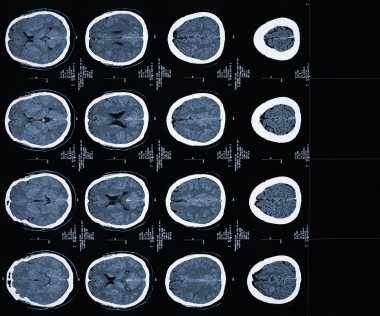

ДИАГНОСТИКА

Проводится осмотр больного, изучается клиническая картина заболевания. Для уточнения диагноза проводятся следующие исследования: компьютерная томография (КТ), магнитно- резонансная томография (МРТ), дополнительно- магнитно-резонансная спектроскопия (МРС), позитронно-эмиссионная томография (ПЭТ), биопсия.

Медицинские процедуры, проводимые при заболевании астроцитома (глиома): Компьютерная томография, Магнитно-резонансная томография, Магнитно-резонансная спектроскопия, Позитронно-эмиссионная томография